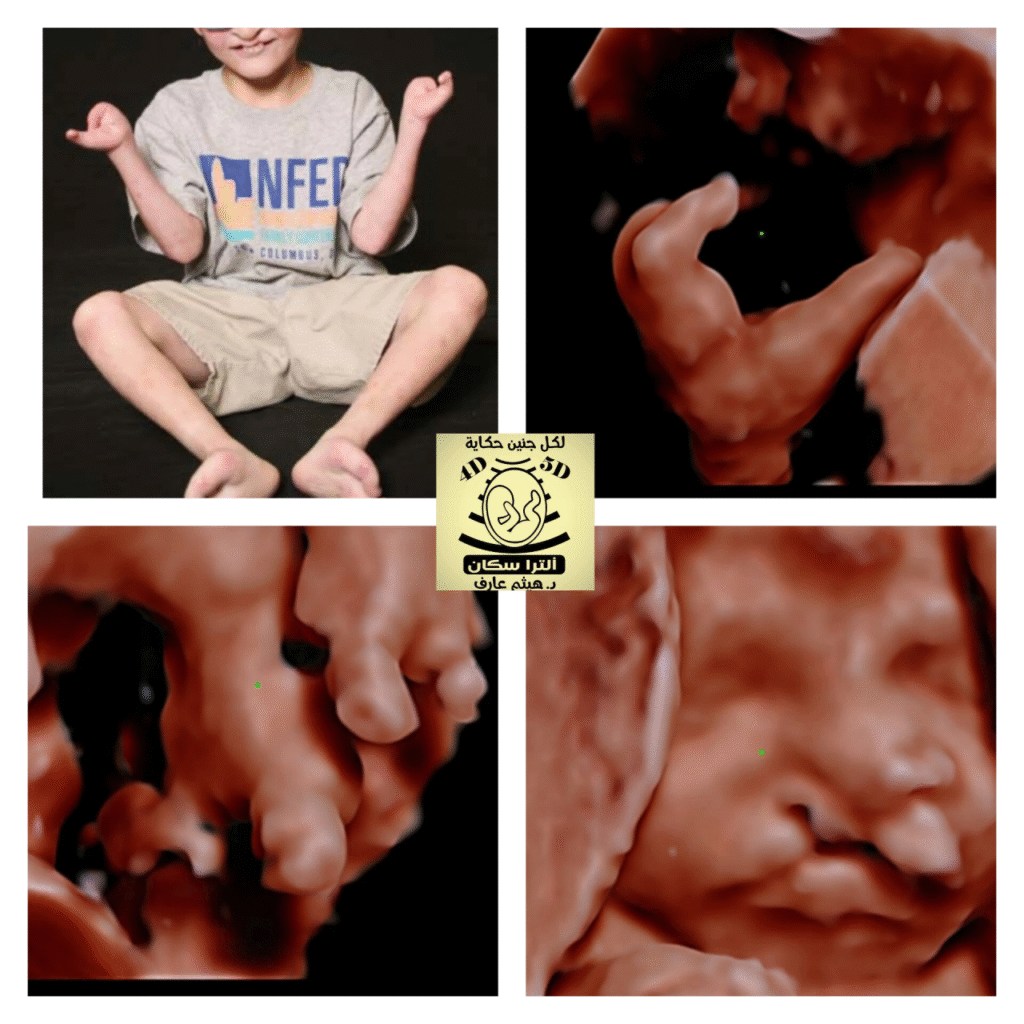

ectrodactyly-ectodermal dysplasia-clefting syndrome ,by DR ALAA OBEID

Limb and facial anomalies are characteristic features of ectrodactyly-ectodermal dysplasia-clefting syndrome ,

hashtag#Ectrodactyly: Malformations of the limbs, also known as split-hand/foot malformations or “lobster-claw” deformities.

hashtag#Clefting: The presence of a cleft lip with or without a cleft palate